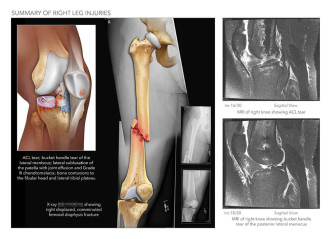

Summary of Left Leg Injuries

Available in high resolution JPEG or PDF formats, 8x10 print, or laminated foam core exhibit board (24x46, 30x40 or 36x48).